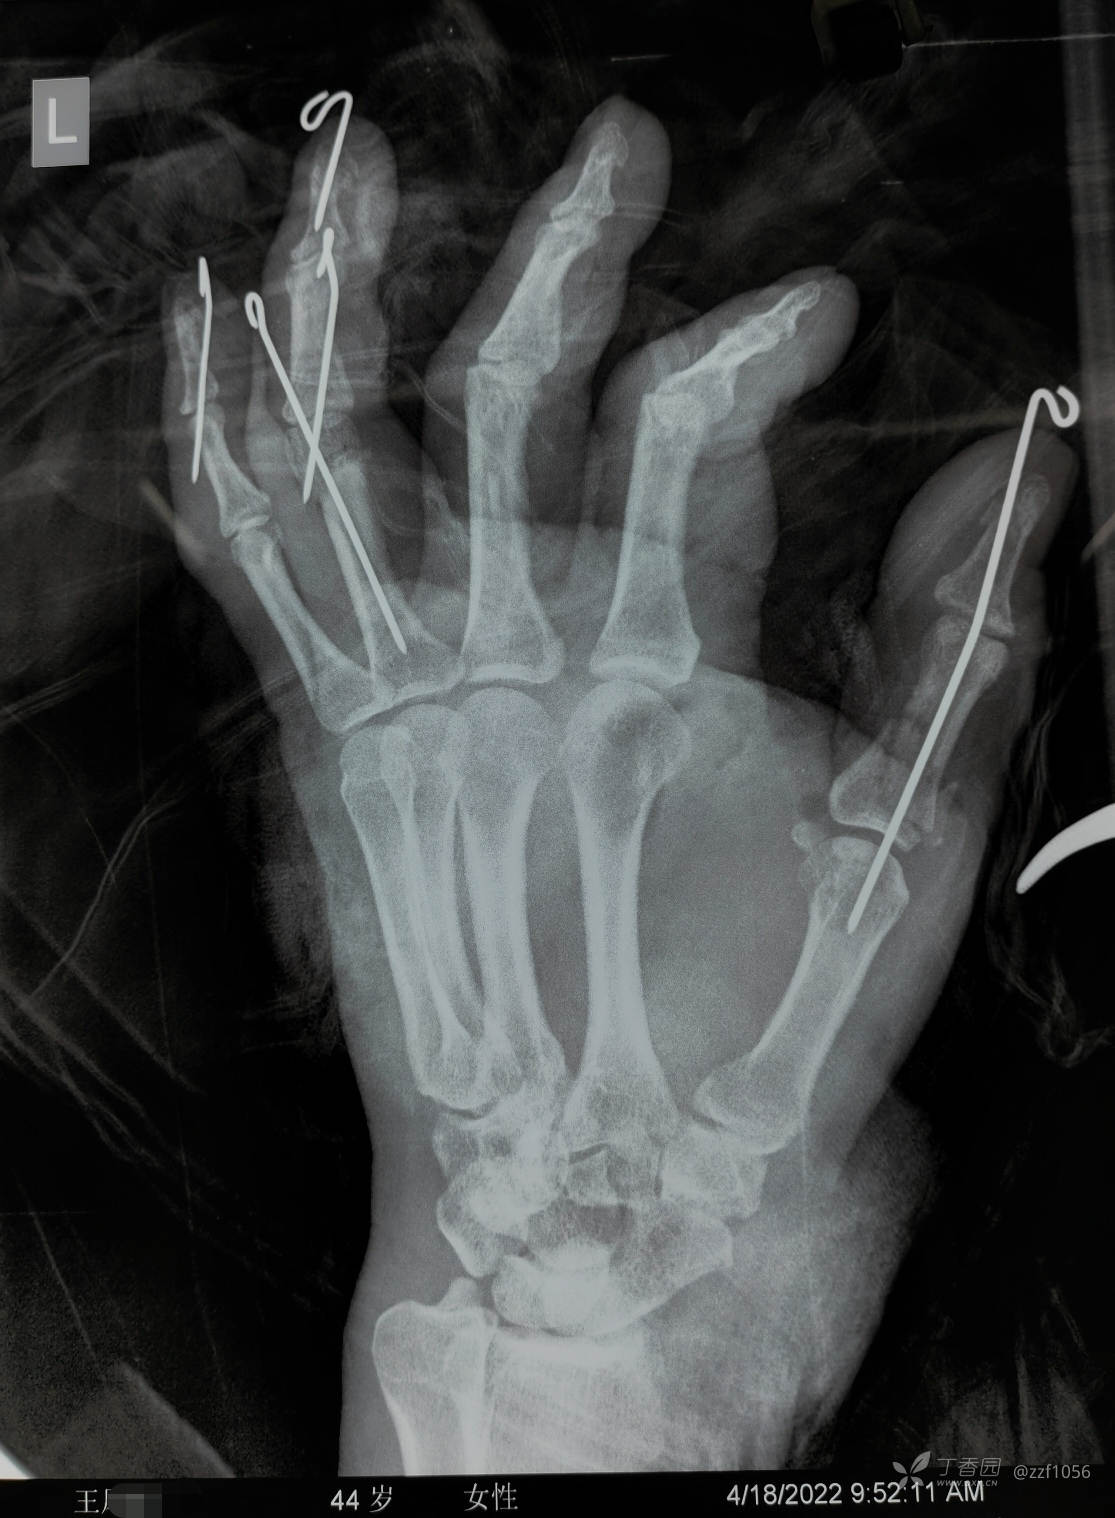

患者王某,女,44岁,两个月前被和面机绞伤左手

急诊手术资料

骨折基本也是闭复穿针固定技术